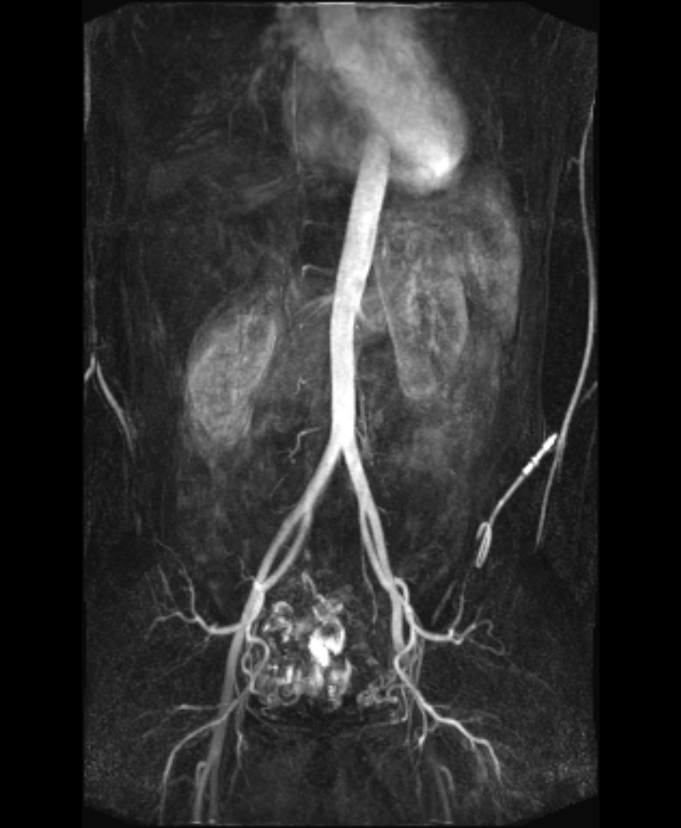

Jedenfalls: Was ihr hier seht – also dieses helle gartenschlauchartige Ding, das sich weiter unten so schön aufzweigt – ist meine Aorta, die Hauptschlagader des Körpers, die sauerstoffreiches Blut aus dem Herzen in die Organe leitet. Der Klumpen ganz oben ist mein Herz, darunter seht ihr rechts und links meine etwas schräg aufgehängten Nieren (was vermutlich damit zu tun hat, dass sich meine Leber auf der linken Seite ein wenig dick macht). Und ganz unten erkennt ihr ein seltsames Gewürm, über das ich noch haltlos mutmaßen werde.

Also wenn ihr mich fragt, sieht meine Aorta total dufte aus. Mit geschlossenen Augen ein kleines bisschen gekrümmt vielleicht, aber zumindest dicht. Was meine ich mit gekrümmt?

Normalerweise verläuft die Aorta ziemlich gerade durch den Körper. Wenn das nicht der Fall ist, ist sie elongiert, also verlängert und stärker geschwungen als sie sein sollte.

Das sieht man oft bei älteren Menschen, deren Gefäße mit der Zeit einfach an Elastizität verloren haben, aber auch wenn zum Beispiel eine Skoliose vorliegt, also eine Verkrümmung der Wirbelsäule. Die Aorta passt sich dann sozusagen einfach an die veränderten Bedingungen an.

Ganz klassisch zeigt sich eine elongierte Aorta aber auch bei Menschen, die eine Bindegewebsstörung haben (wie das Ehlers-Danlos-, das Marfan-Syndrom oder die Hypermobility Spectrum Disorder). Verrückt! Denn ich habe ja eine Bindegewebsstörung – aber offensichtlich, wenn überhaupt, nur eine ganz minimalwinzig krumme Aorta. Trotzdem nehme ich sie mal als Aufhänger für einen wichtigen Reminder:

Mal ist eine elongierte Aorta harmlos, in anderen Fällen kann sie jedoch das Risiko von Komplikationen wie Aortenaneurysmen erhöhen. Ergo – ihr wisst, was jetzt kommt: Geht! Zur! Kontrolle!

Das mysteriöse Gewürm

Aber was ist eigentlich dieses Gewürm da ganz unten im kleinen Becken? Mein erster Gedanke dazu war: Genau DA habe ich in letzter Zeit ständig Schmerzen. Also könnte das vielleicht venöses Gefäßgewürm sein, so verknotet, wie das aussieht. Also im Klartext: Krampfadern. Eine mögliche Erklärung: pelvines Stauungssyndrom, also Klappendefekte in den Venen des Beckens und der Eierstöcke – haben übrigens auch zwei weitere Ärzte vermutet, die ich kenne. Dagegen spricht allerdings, dass die Aufnahmen in der arteriellen Phase gemacht wurden (also kurz nachdem mir Kontrastmittel injiziert wurde) – denn es ging ja um die Darstellung der größten Arterie überhaupt, der Aorta. Venen sollten also nicht zu sehen sein, wenn ich das richtig kombiniere. Doch wenn dieses Gewürm Arterien sind, dann… warte ich lieber auf den Arztbrief und trink ne heiße Schokolade. Es wäre natürlich toll, wenn ich eine passende Erklärung für meine Beschwerden bekäme, aber ich schlag mich natürlich nicht um irgendwelche Auffälligkeiten.

Update: Meine Aorta ist laut Facharzt wirklich dufte. Aber mein Gedärm wird nur halbherzig versorgt, da ich eine Stenose in der Arteria mesenterica habe (das unterbrochene Zipfelchen, das bauchwärts aus meiner Aorta rauskommt, zu sehen in der Sagittalebene). Eventuell durch Verklebungen im Bauch durch die vielen Kaiserschnitte? Verrückt, denn genau deshalb hab ich mir vor einer Weile eine Überweisung für eine Darmdurchleuchtung geholt – um schauen zu lassen, WO es klebt. Ich merke ja, DASS was klebt. Trotzdem gut und richtig, dass ich Kaffeesatzlesen nur bei mir selbst betreibe. Ein bisschen wie der Versuch, Landkarten zu verstehen, um am Ende im Graben zu landen und über sich selbst zu schmunzeln. ☺️